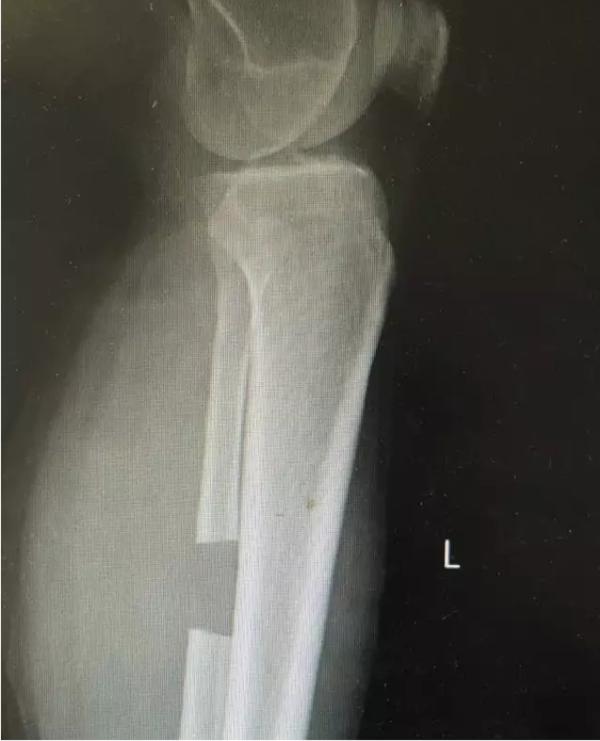

膝关节不均匀沉降术后患者X线片(下图)

术后图如下: